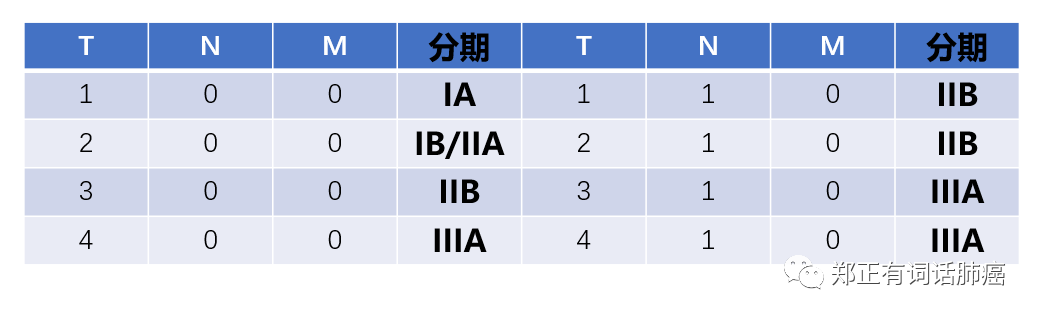

在这个研究中,作者基于一个多中心的数据库筛选肺腺癌病例,即那些接受手术切除、且病理分期介于pN0-1M0的患者。

病理分期介于IA~IIIA之间。